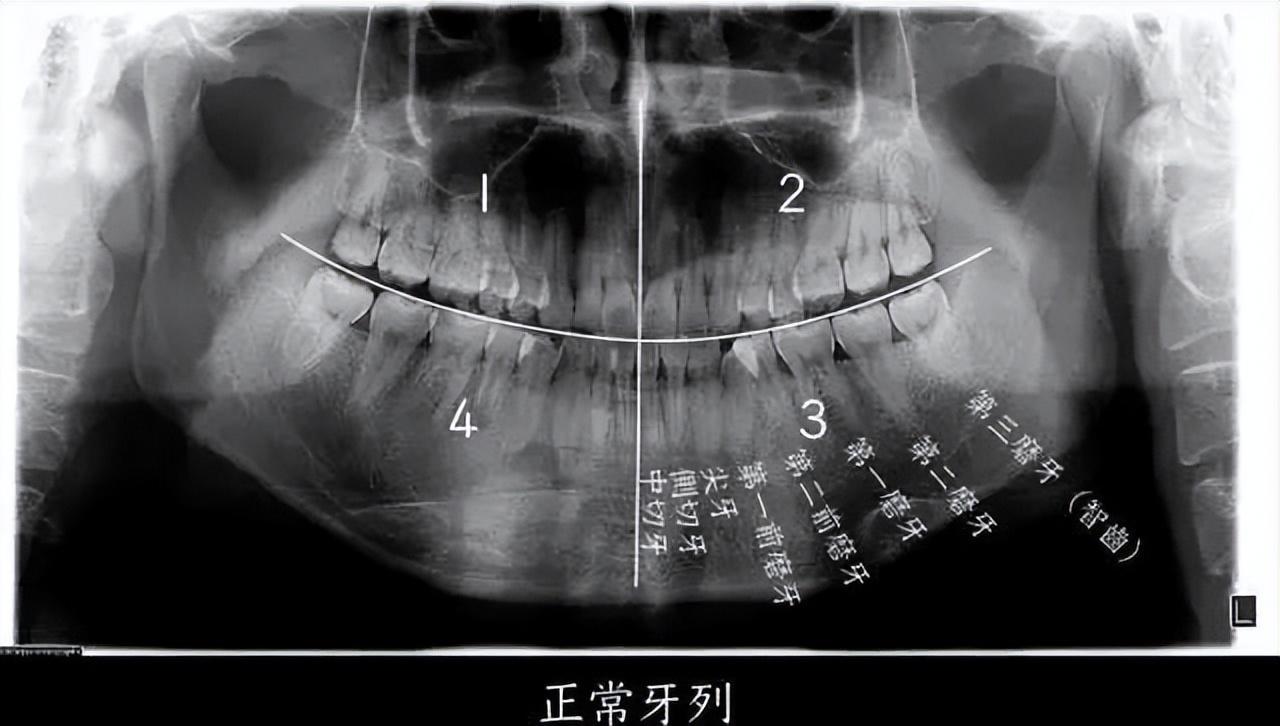

图源:浙江大学医学院附属第二医院何剑亮医生

如果把一个正常成年人的口腔分为左上、左下、右上、右下四个区域的话,每个区域会有 8 个牙齿,长在最后的第8颗牙齿,就是我们口中的“智齿”,即第三磨牙。